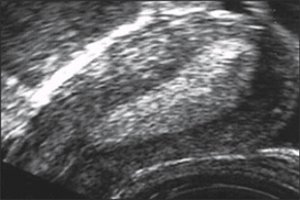

Известно, что неполноценная секреторная трансформация эндометрия является следствием недостаточного влияния прогестерона. Эхографически это проявлялось в повышении эхогенности только в периферических отделах М-эхо с гипоэхогенной зоной в центре (рис. 1).

Рис. 1. Неполноценная секреторная трансформация эндометрия.